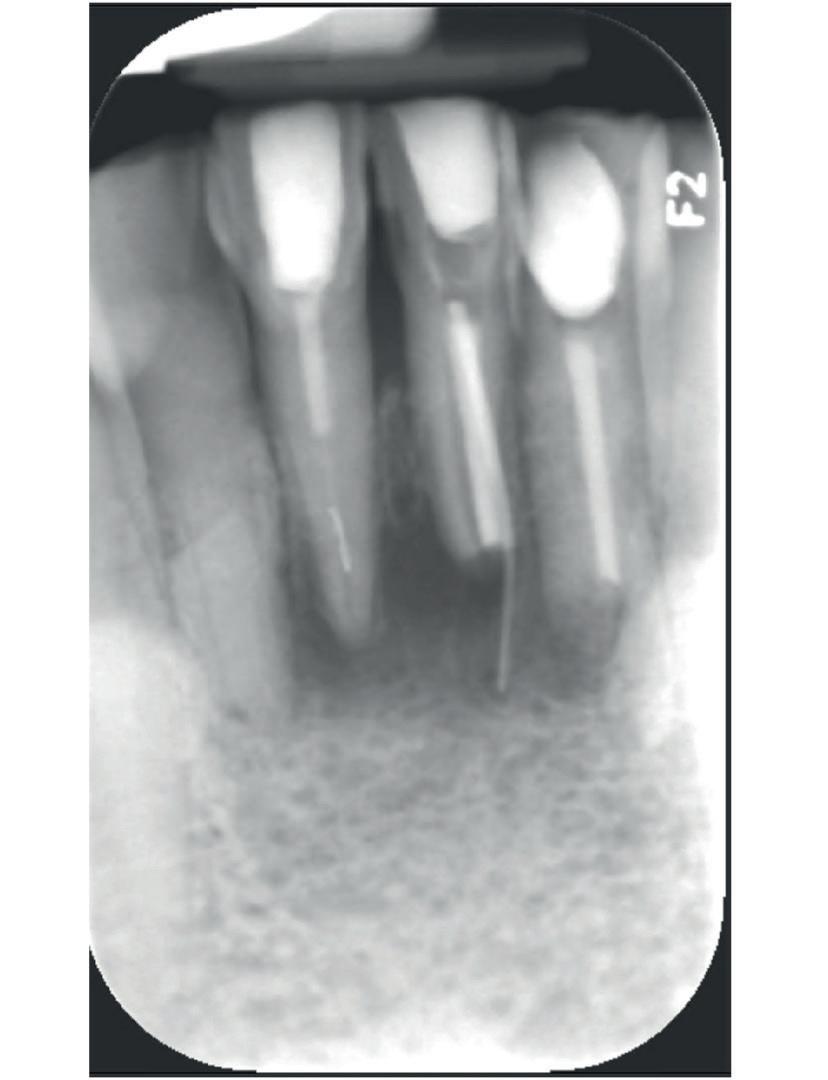

Bij klinisch en röntgenologisch onderzoek viel echter op dat radix van de 12 en 22 een convergerende (de radices staan dan naar mesiaal en naar elkaar toe) in plaats van divergerende (radices staan dan van elkaar af) stand had. Door deze convergerende stand van de radices was er in mesio-distale zin geen ruimte voor twee implantaten ter plaatse van de 11 en 21. Er werd daarom besloten, in tegenzin

1. Retainer met twee frontelementen

2. OPT radices 12 en 22 convergeren

3. Vaste apparatuur voor torque 12 en 22

4. OPT radices 12 en 22 divergeren na orthodontische behandeling

van de patiënt, om eerst weer vaste apparatuur terug te plaatsen om de radices in een divergerende stand te plaatsen. Gelukkig verliep deze behandeling voorspoedig. (afbeelding 2 -4). Het volgende behandelplan werd gemaakt: